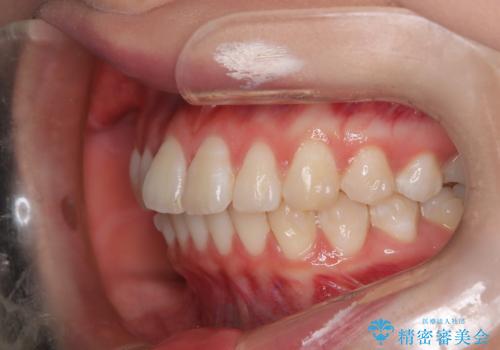

前歯のガタつきを治したい 翼状捻転マウスピース矯正

- 上顎前歯の突出、がたつき(翼状捻転)を主訴に来院されました。当院では総合歯科医療が可能であるため、矯正前処置として虫歯治療・歯周治療、親知らず抜歯を施行しました。その後、非抜歯かつ口元が出ないようなマウスピース治療を行いました。仕事柄、1日の装着時間が短くなってしまう時期もありましたが、患者様と相談しながら問題なく終了しています。